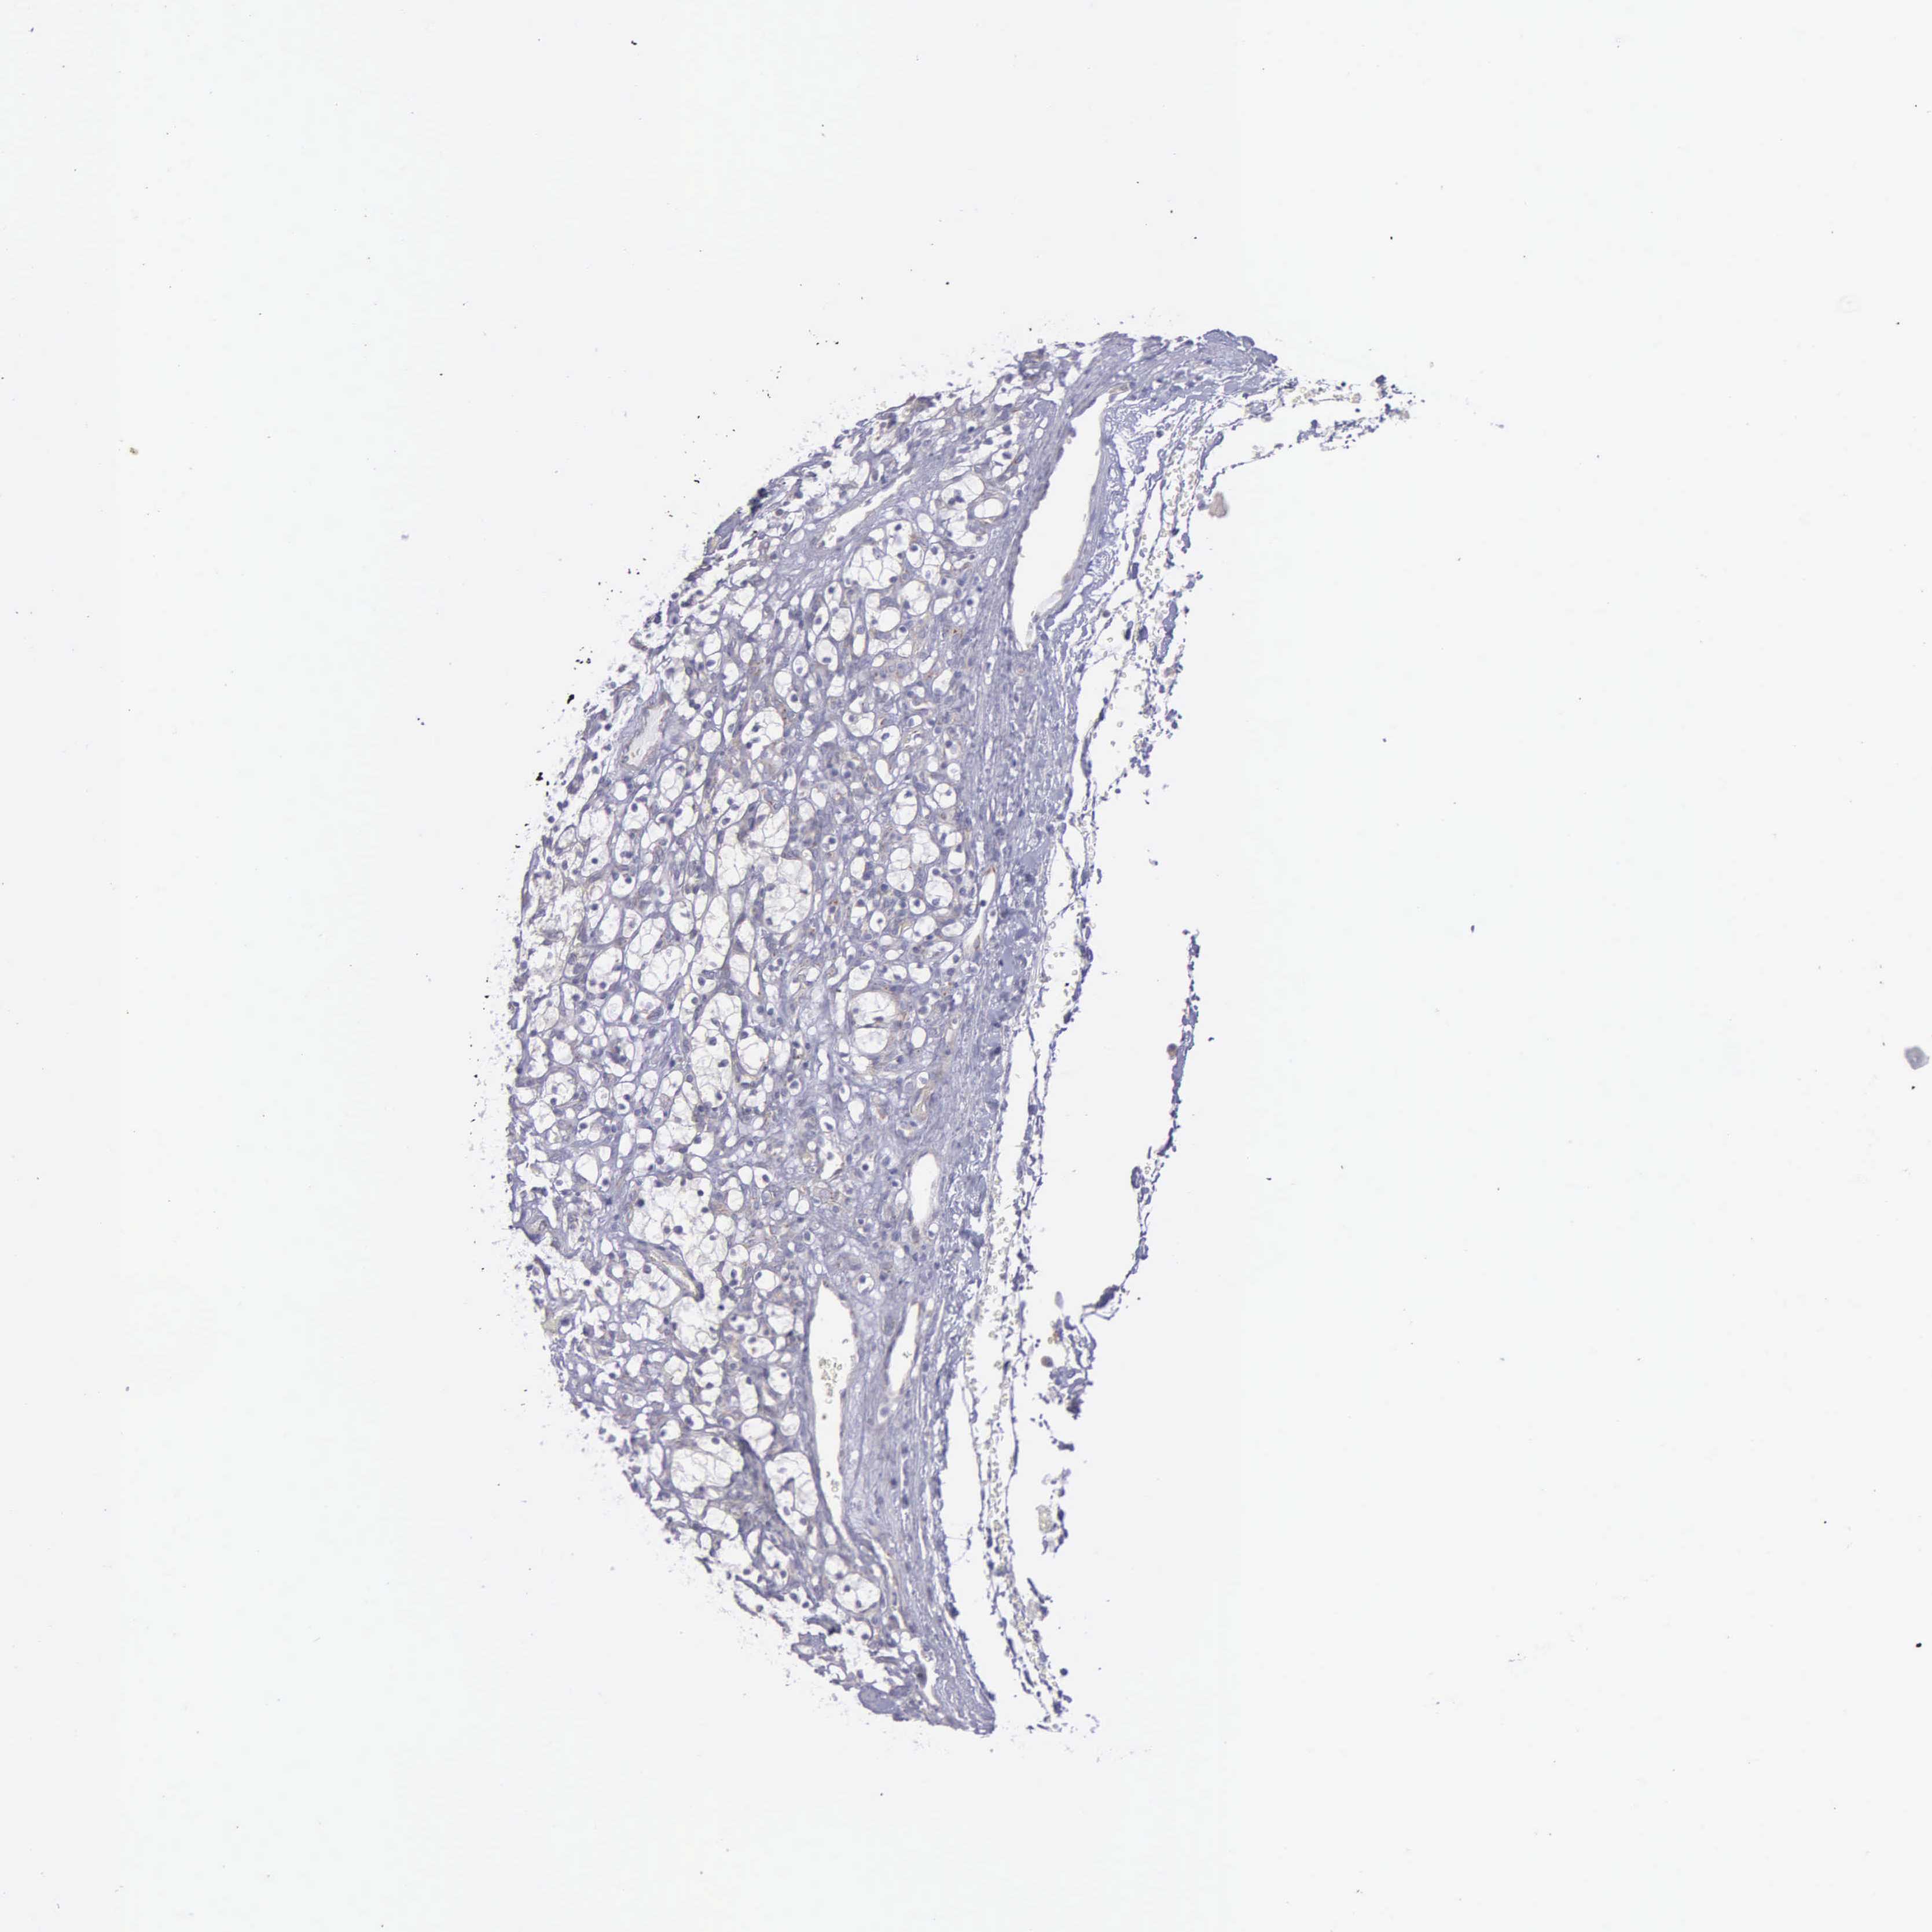

KIDNEY RENAL CLEAR CELL CARCINOMA (VALIDATION) - Interactive survival scatter ploti

The Survival Scatter plot shows the clinical status (i.e. dead or alive) for all individuals in the patient cohort, based on the same data that underlies the corresponding Kaplan-Meier plots. Patients that are alive at last time for follow-up are shown in blue and patients who have died during the study are shown in red.

The x-axis shows the expression levels (FPKM) of the investigated gene in the tumor tissue at the time of diagnosis. The y-axis shows the follow-up time after diagnosis (years). Both axes are complimented with kernel density curves demonstrating the data density over the axes. The top density plot shows the expression levels (FPKM) distribution among dead (red) and alive patients (blue). The right density plot shows the data density of the survived years of dead patients with high and low expression levels respectively, stratified using the cutoff indicated by the vertical dashed line through the Survival Scatter plot. This cutoff is automatically defined based on the FPKM cutoff that minimizes the p-score. The cutoff can be changed by dragging the vertical line or by entering a cutoff value in the square labeled "Current cut-off".

Under the Survival Scatter plot the p-score landscape (black curve; left axis) is shown together with dead median separation (red curve; right axis). Dead median separation is the difference in median mRNA expression between patients who have died with high and low expression, respectively. It is calculated as follows: median FPKM expression of dead patients with high expression - median FPKM expression of dead patients with low expression. This is intended to aid the user in visually exploring custom cutoffs and the associated p-scores and dead median separation.

Individual patient data is displayed and can be filtered by clicking on one or more of the category buttons on the top of the page. Categories describing expression level and patient information include: high, low, alive, dead, female, male and tumor stages. The scale of the x-axis can be toggled between linear and log-scale by clicking on the "x log" button. Mouse-over function shows TCGA ID, patient information and mRNA expression (FPKM) for each patient.

& Survival analysisi

Kaplan-Meier plots summarize results from analysis of correlation between mRNA expression level and patient survival. Patients were divided based on level of expression into one of the two groups "low" (under cut off) or "high" (over cut off). X-axis shows time for survival (years) and y-axis shows the probability of survival, where 1.0 corresponds to 100 percent.

SYNJ2BP is validated prognostic, high expression is favorable in Kidney Renal Clear Cell Carcinoma (validation)

Best expression cut offi

Based on the FPKM value of each gene, patients were classified into two groups and association between prognosis (survival) and gene expression (FPKM) was examined. The best expression cut-off refers the FPKM value that yields maximal difference with regard to survival between the two groups at the lowest log-rank P-value. Best expression cut-off was selected based on survival analysis .

When clicking on this number, the vertical dashed line indicating cut-off, the interactive survival plot, and the Kaplan-Meier curve will be adjusted to show results based on the best expression cut-off.

: 11.38

TCGA RNA samplesi

RNA-seq data is reported as average FPKM (number Fragments Per Kilobase of exon per Million reads), generated by the The Cancer Genome Atlas (TCGA) .

Normal distribution across the dataset is visualized with box plots, shown as median and 25th and 75th percentiles. Points are displayed as outliers if they are above or below 1.5 times the interquartile range. FPKM values of the individual samples are presented next to the box plot.

Average pTPM 13.2

Number of samples 100